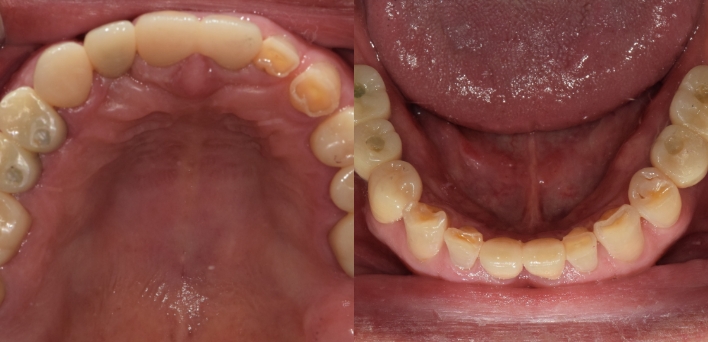

임플란트 : 손 ** 님 (50대)

치아가 있다는게, 아직도 정말 꿈만 같아요.

Before Before

2020.02.30

After After

※ 더서울치과의원은 의료법을 준수하며 위 케이스는 실제 환자의 동의를 얻은 사례로 치료 전, 후가 동일한 환경에서 촬영되었습니다.

환자 케이스에 따라 부작용이 발생할 수 있습니다. 이 부분은 의료진의 충분한 상담과 체크를 통해 예방하고 줄일 수 있습니다.

[임플란트 부작용] 수술 후 관리가 소홀할 경우 출혈, 주위염 등의 부작용이 발생할 수 있어 구강 위생을 철저히 유지하고, 정기적인 검진을 통해 상태를 점검하는 것이 중요합니다.

환자 특징

환자 특징01무치악 상태

환자 특징02수년간 무치악으로 지내심

임플란트가 불가능할것이라

생각하고 내원

위, 아래 6개씩 식립

디지털 풀아치 임플란트

임플란트 Before & After